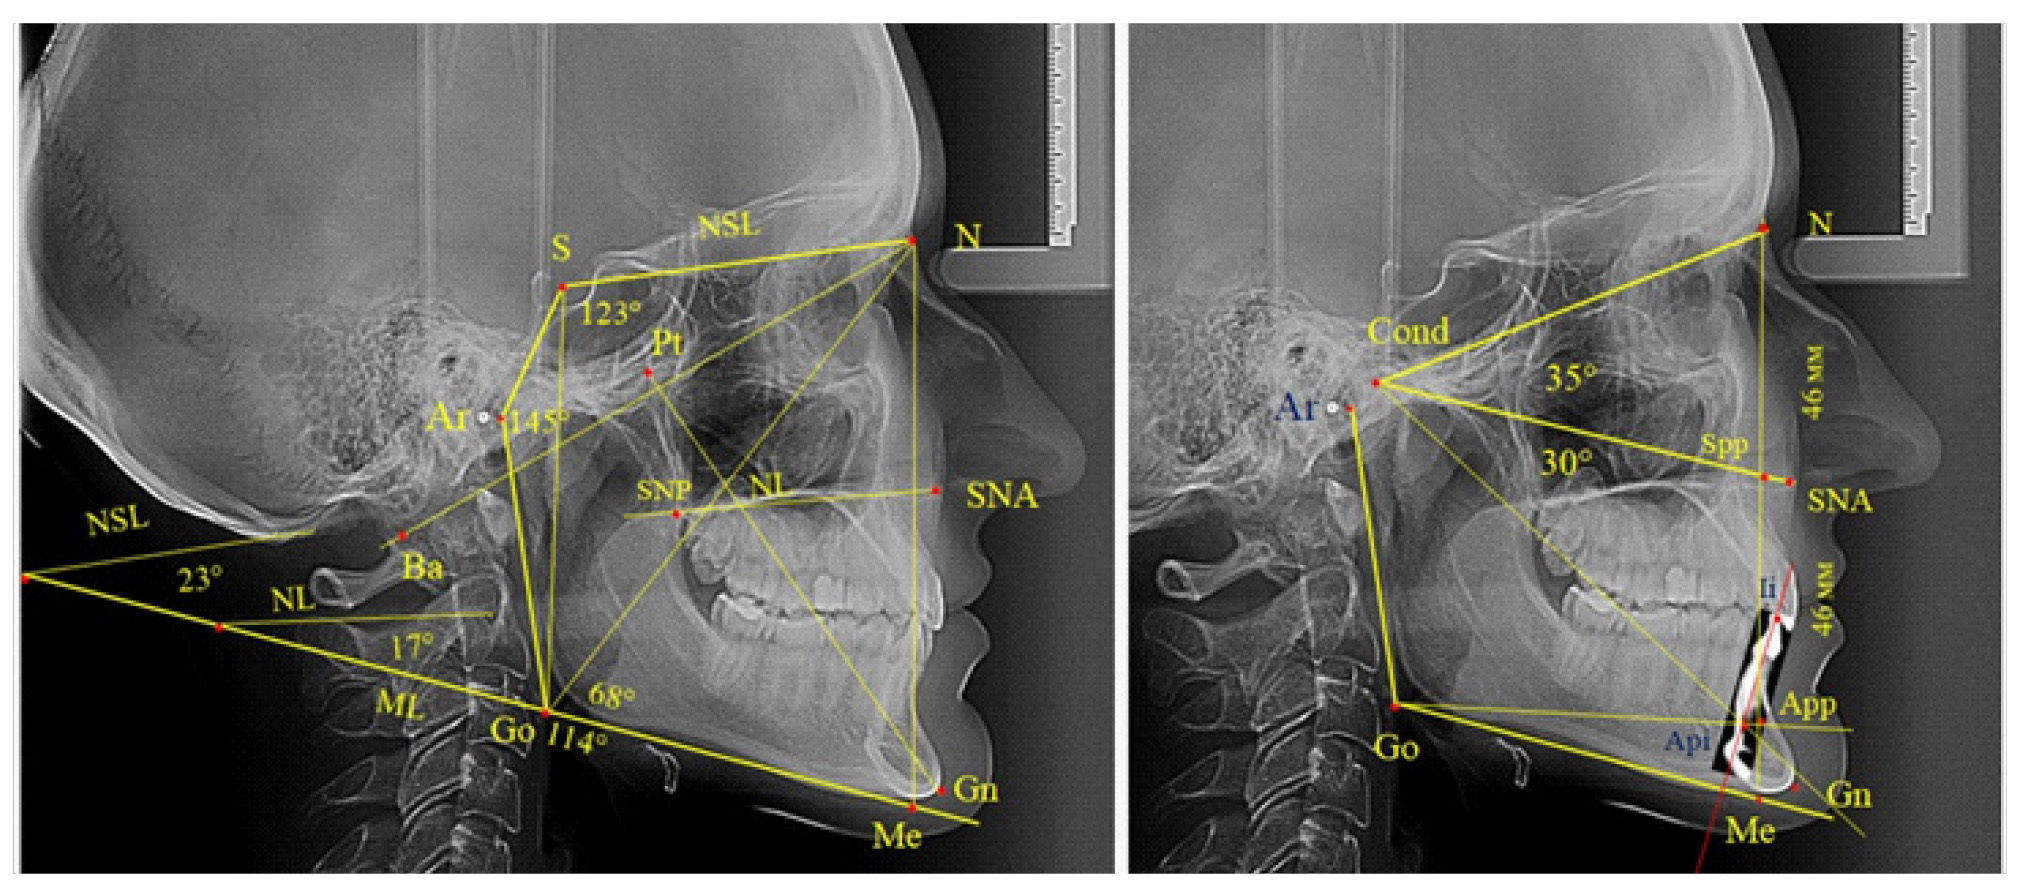

Основу анализа традиционно составляла суммарная составляющая трех углов Bjork, которая включала углы N-S-Ar, S-Ar-Go и Ar-Go-Me, которые ограничивают костные структуры линевого отдела головы, и полученная величина определяет типологические особенности роста лица. Нижний нижнечелюстной угол образован линиями N-Go и Go-Me. При построении лицевого угла Ricketts проводили линию N-Ba и линию Pt-Gn, с последующим измерением внутреннего угла.

Также к показателям типа роста относили углы, образованные мандибулярной плоскостью, с линией основания черепа (NSL-ML) и основания верхней челюсти (NL-ML). Кроме определения угловых параметров оценивали линейные показатели, в частности проводили сравнение передней высоты лица (N-Me) с задней высотой (S-Go).

Нередко при анализе телерентгенограммы на верхушку корня медиального нижнего резца наслаиваются контуры соседних зубов, и данный ориентир недостаточно четко определяется. В подобных случаях выделяли фрагмент зуба из томограммы с последующим наложением и совмещением с телерентгенограммой.

Данная методика позволяла определять положение верхушки корня медиального нижнего резца, полученный ориентир в ортодонтии принято обозначать как Api (apicalе inferior), а точка режущего края нижнего резца обозначалась как Ii. Для оценки вертикальных параметров оценивали угол N-Cond-SNA, который использовали для определения параметров назального отдела. При этом точка Cond соответствовала верхнему полюсу суставной головки. Угол SNA-Cond-Api определял угловые параметры гнатического отдела лица без учета размеров подбородка, который является наиболее вариабельной структурой нижней челюсти. Альвеолярную часть нижней челюсти отделяли от подбородочной части линией, соединяющей конструктивную точку угла нижней челюсти Go с верхушкой корня нижнего резца (Go-Api).

Вертикальная линия передней высоты лица (N-Me), после ее пересечения с линией Cond-SNA, определяла положение точки Spp, при этом вертикаль N-Spp использовалась в качестве оценки высоты назального отдела лица. Продолжение линии Go-Api до пересечения с линией N-Me позволяла определить положение конструктивной точки Арр и оценить линейные размеры гнатической части лица по величине вертикали Spp-Арр (рис. 1).

В одном случае [(4,17 ± 4,08) %], определялось патологическое увеличение назального отдела лица при уменьшении гнатической его части. Некоторые варианты ТРГ пациентов с глубокой резцовой окклюзией представлены на рис. 6.

Рис. 6. Варианты ТРГ с уменьшенными размерами носового отдела и оптимальными (а) и укороченными (б) размерами гнатической части лица при глубокой резцовой окклюзии

Вертикальная резцовая дизокклюзия (открытый прикус) была проанализирована на 11 телерентгенограммах. При этом отмечались варианты как с оптимальными, так и увеличенными параметрами гнатической части лица при различных типах роста назального отдела, что представлено на рис. 7.

Рис. 7. Сравнительный анализ ТРГ при увеличенных размерах гнатической части с оптимальными (а), укороченными (б) и увеличенными (в) размерами носового отдела лица и вертикальной резцовой дизокклюзией